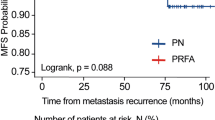

Gervais et al. report a retrospective series of 100 renal tumours treated with RFA. One hundred percent of SRM <3 cm, 92% of 3–5 cm masses and 25% of masses >5 cm were treated successfully [1, 2]. Zagoria et al. demonstrate that with each 1 cm increase in diameter above 3.6 cm, the likelihood of recurrence-free survival decreases by a factor of 2.19 and recommends caution when treating tumours >4 cm [8]. Olweny et al. compare the 5-year outcomes for RFA vs. PN in T1a-treated RCC and report 97.2% vs. 100% (p = 0.31) cancer-specific survival, 97.2% vs. 100% (p = 0.31) overall survival and 91.7 vs. 94.6% (p = 0.96) local recurrence-free survival [9]. Psutka et al. report on 185 patients with T1 RCC followed for a mean of 6.43 years. The overall disease-free survival rate was 88.6% (92.3% T1a and 76.3% for T1b), and only 13% of patients were retreated for recurrence [10]. Please refer to Table 6.1 for additional results.

6.9 Long-Term Follow-Up

Several studies have matured to demonstrate long-term efficacy very comparable to that of PN for SRM. Recently, Olweny et al. showed that the 5-year oncologic outcomes of RFA vs. PN in T1a-treated patients with RCC were similar, both having a cancer-specific survival rate greater than 95% [9]. However, PN still remains the standard of care secondary to the lack of studies demonstrating long-term outcomes of TA. With the improvement of provider experience and the increased availability of long-term outcome studies, TA is becoming more widely accepted as a potential alternative for the treatment of solid SRM.